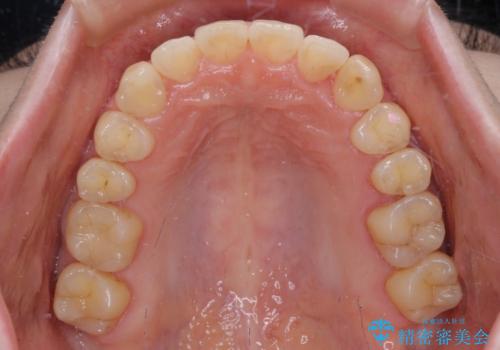

思っていた以上に上顎歯列を後方に移動させることができ、すっきりとした口元に仕上げることができました。

診査を行ったところ、下顎前歯が1本欠損しており、下顎歯列が上顎よりも小さくなっていることで、上顎にデコボコが生じていました。

口元を見ると抜歯をして突出感を改善するような状態ではなかったため、上顎歯列のデコボコを整えて、歯列全体を後方に移動させることでバランスを取ることとしました。